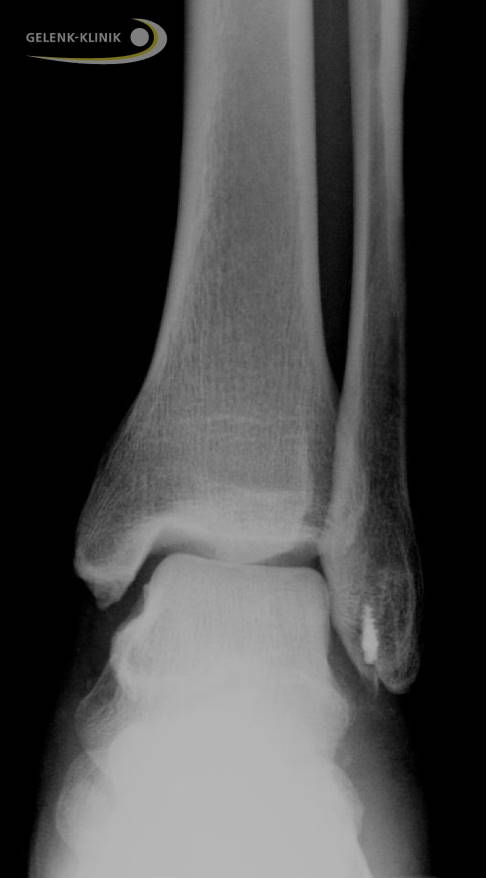

Eine frühe Sprunggelenksarthrose ist die Folge. Wenn das Außenband im Sprunggelenk durch konservative Behandlung nicht von alleine wieder heilt, kann eine Operation die Bandfunktion wiederherstellen.

Eine Überbeweglichkeit des Sprunggelenks kann zu einer frühen Sprunggelenksarthrose führen. Die Markierung zeigt eine deutliche Verschmälerung des Gelenkspalts im oberen Sprunggelenk aufgrund des fehlenden Knorpels. © Gelenk-Klinik